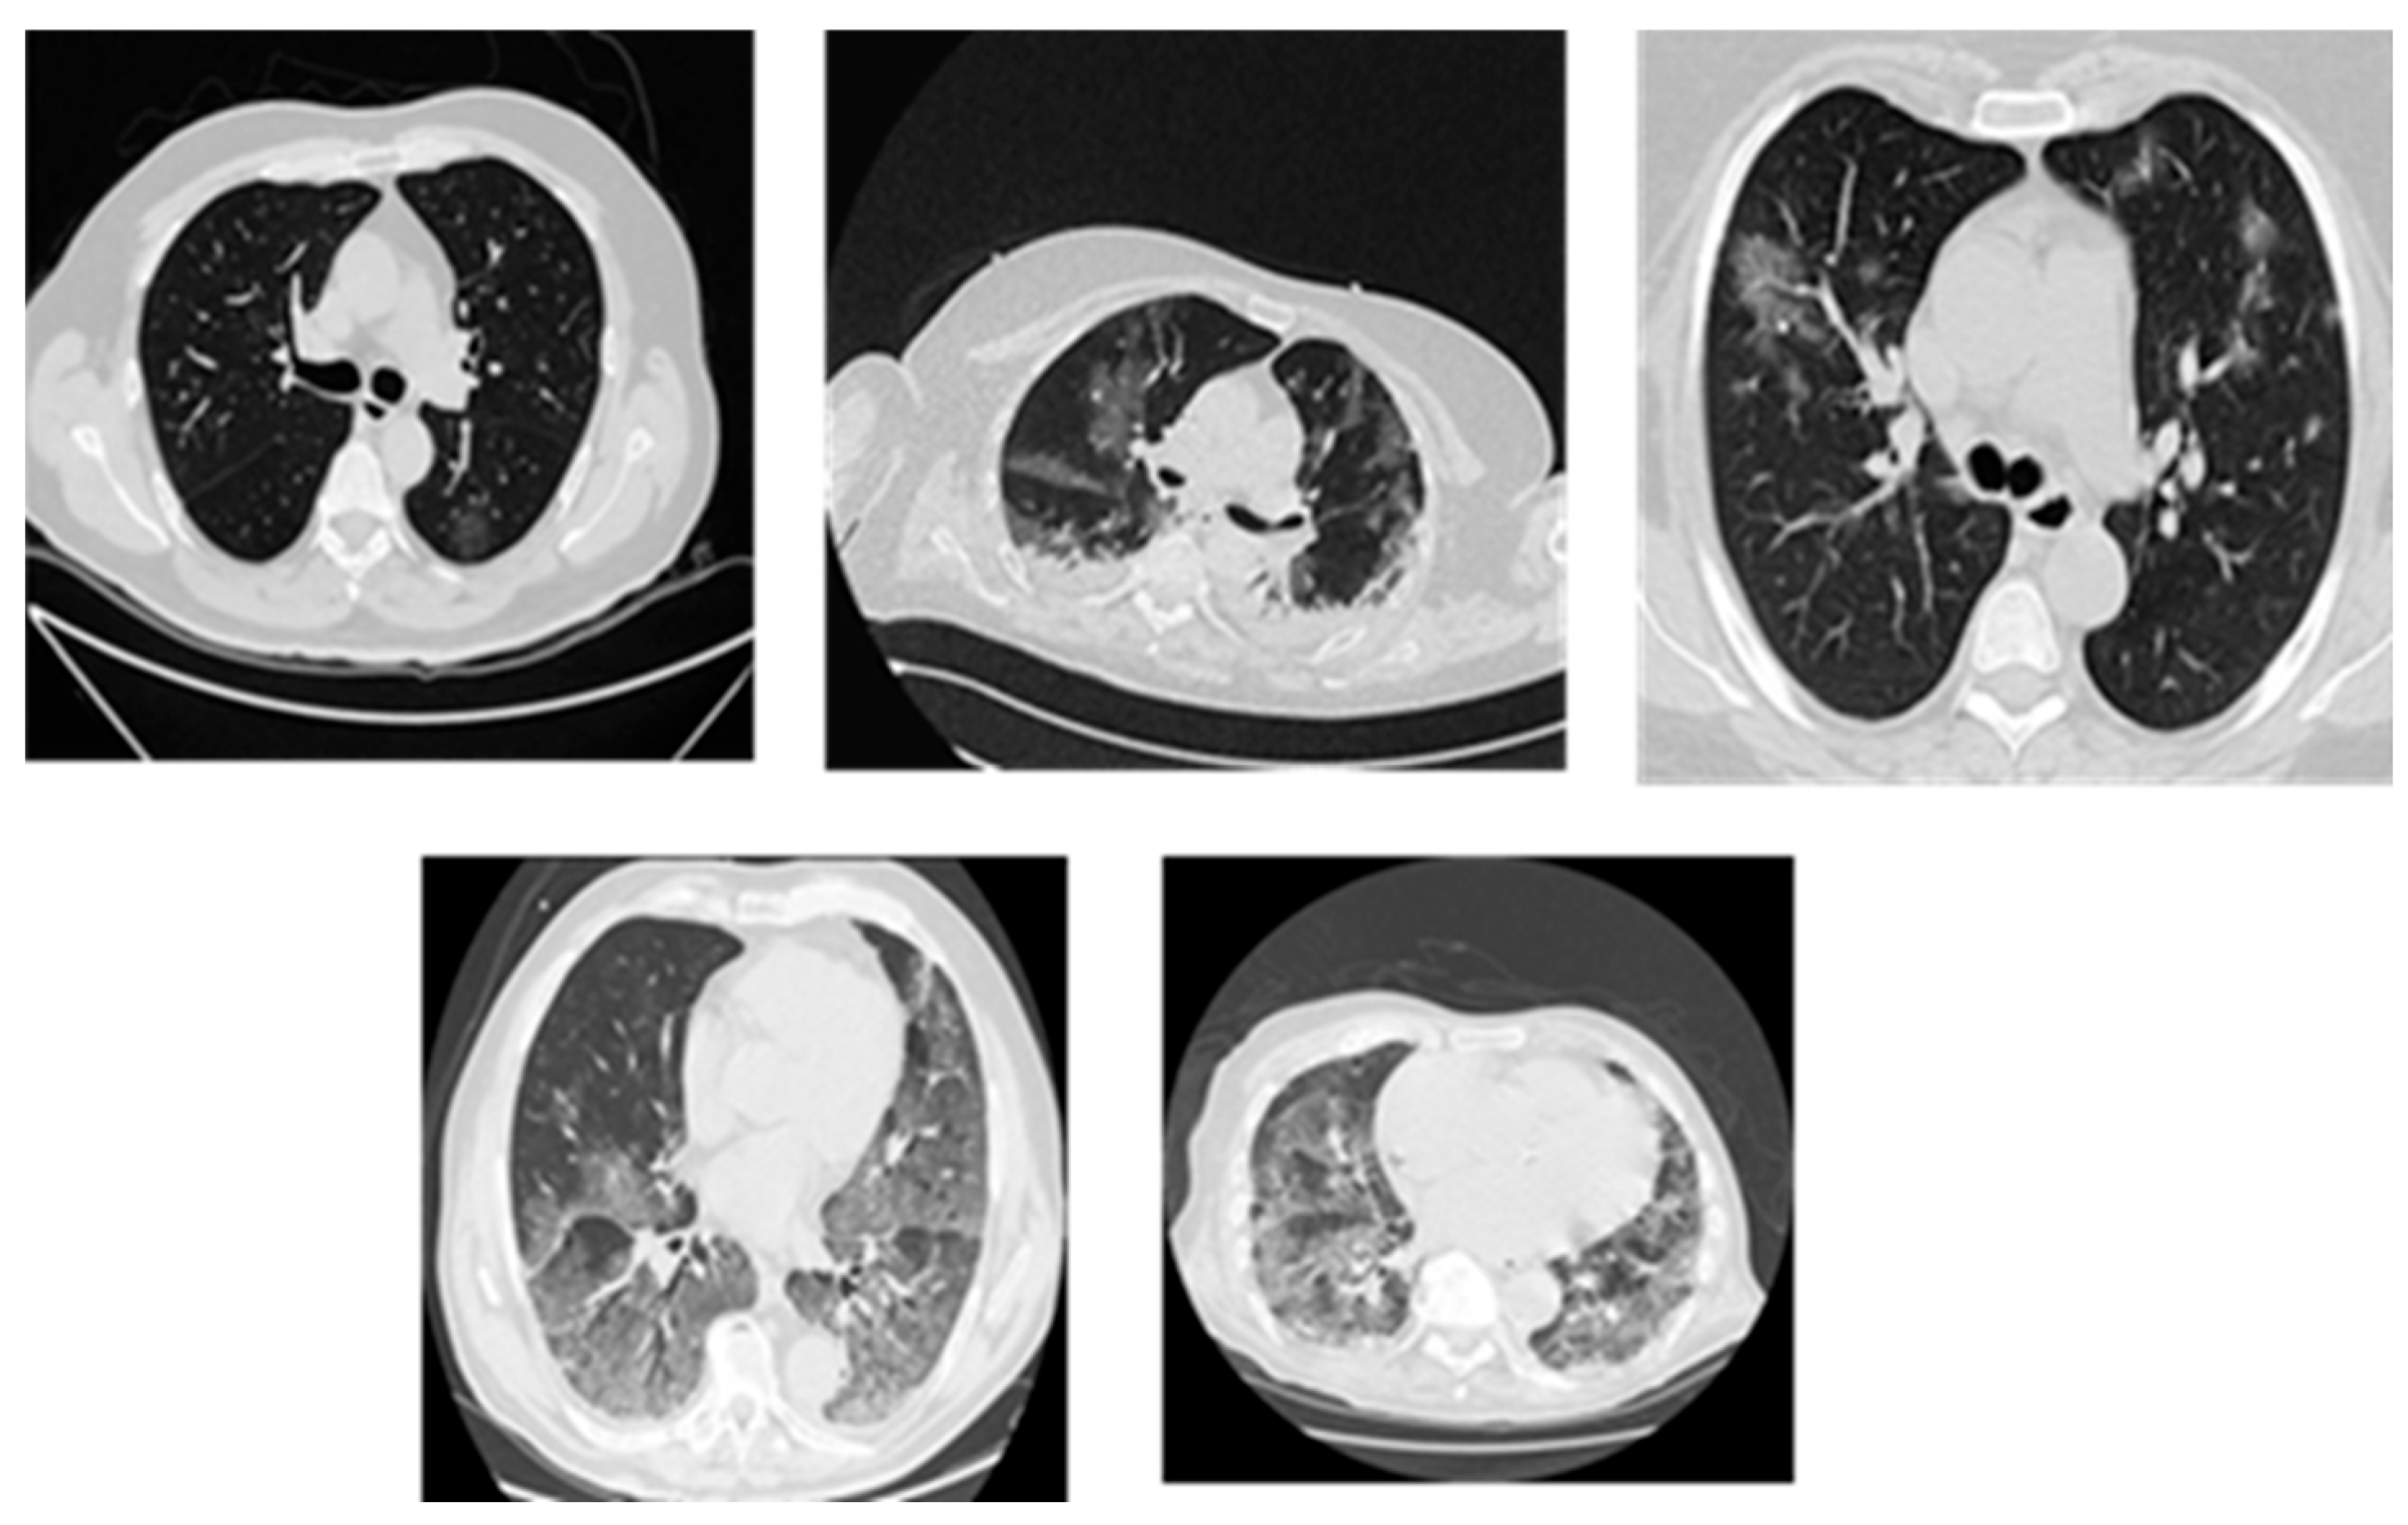

Lung cancer diagnosis, as shown in Figure 1, becomes more difficult due to its diverse nature as well as the range of growth patterns and visual characteristics across various cancer types. Several distinct types of lung cancer may present themselves differently within a single imaging examination [37]. The dominant subtype usually takes priority in diagnosis procedures performed by radiologists, yet this practice omits critical details from less obvious subtypes. Acute and complete subtype identification and characterization enable medical professionals to select optimal treatment solutions. The correct determination of benign versus malignant status depends heavily on evaluating size, growth rate, and density characteristics in nodules [24].

The Iraqi Lung Cancer Image Dataset (ILCID) utilized in this research was collected from three large Iraqi medical metropolitan centers, which were diverse and clinically reliable. The three hospitals are Oncology and Alternative Nuclear Medicine Hospital in Mosul (1500 images), Al-Zahrawi Special Hospital in Mosul (800 images), and Shilan Special Hospital in Duhok (700 images), whereby a total of 3000 high-resolution lung CT scan images were recorded according to ethical approval from the Iraqi Ministry of Health, Nineveh Health Directorate, Training and Human Development Center (Ethical ID Code: 2023118, approved in 7 June 2023). The collection of data started in October 2022 by obtaining formal permission from each institution. All scans were made with the Philips Brilliance barefoot CT Scanner (model 2019), where the image quality and the imaging parameters were standardized to ensure uniform recorded data. The dataset has a wide range of lung cancer manifestations, such as various tumor volumes, types, and phases of the disease (early, intermediate, and advanced). Each scan was annotated manually by expert radiologists who gave each scan accurate segmentation masks to enable powerful model training and assessments. Inclusion criteria were also very strict to make sure that it is clinically relevant and includes various types of cancer (small-cell and non-small-cell lung cancer) and diverse patient demographics to improve the generalization. Before developing the model, there was an extensive preprocessing pipeline that eliminated artifacts and low-quality scans and normalized image properties, leaving a high-quality dataset free of problems and ready to be used in advanced computer-aided diagnosis. Figure 5 shows samples of the collected dataset.

Figure 1. Lung cancer nodules in CT scans.

Figure 5. Samples of the collected dataset.